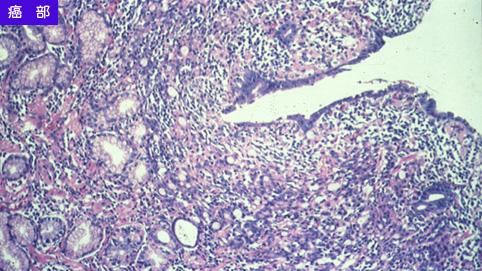

疾病(病理主体)的分类恶性上皮性肿瘤/印戒细胞癌

部位(按器官分)胃(部位)/胃角

检查方法病理切片(微观)

肿瘤的肉眼分类0型(表在型)/IIc型(IIc+III)

肿瘤最大直径30~34

肿瘤的深度m